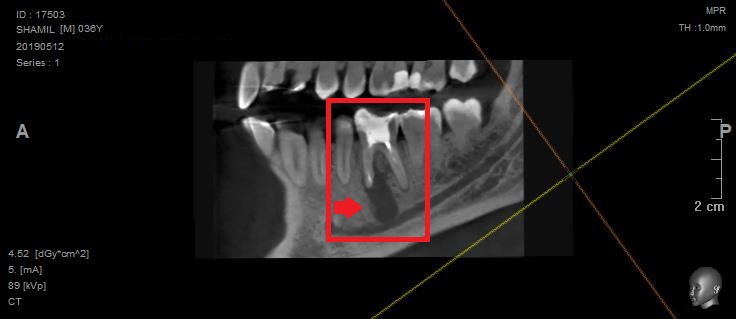

На этом снимке видно, что вокруг корня зуба образовалась киста, которая заполнена кровяной массой.

Если всмотреться в этот снимок, то можно увидеть участок, где киста пробила кость. Именно это и стало причиной болей и воспаления на челюсти.

Киста — защитная реакция организма, с помощью которой организм отгораживается о проблемного зуба. Первичная причина возникновения проблемы – сломанный фрагмент инструмента, который остался в зубе, при лечении его 19 лет назад. Оставшийся в зубе инструмент создает условия для воспалительного процесса.

На этой проекции видно повреждение поверхности кости от кисты.

(отверстие, которое вы видите слева, чуть ниже — место выхода нижнечелюстного нерва)